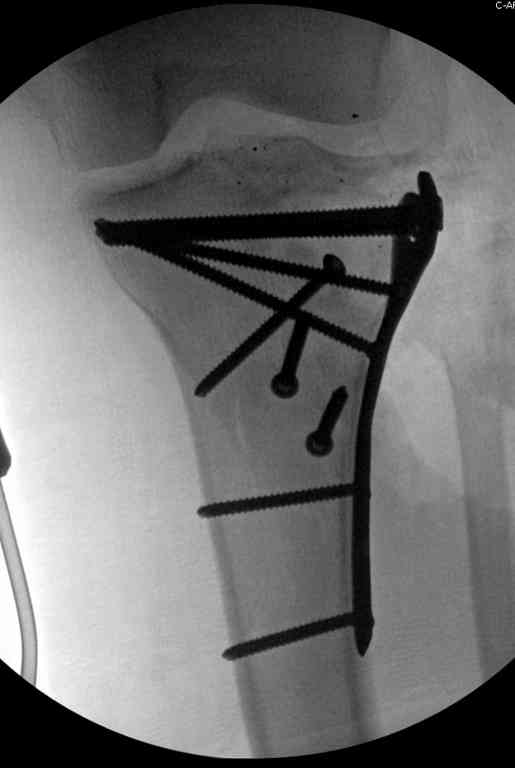

Тамошние доктора выполнили ПХО с удалением фрагментов латерального мыщелка бедра. Наложен АВФ. По возвращению в Украину через 1,5 месяца АВФ демонтирован. И так как смещение фрагментов бедра не устранено, было принято решение после заживление ран от стержней выполнить МОС. Не сколько для четкой анатомической репозиции сколько для подготовки к установке эндопротеза в будущем. Что и было выполнено 10 августа. Интраоперационная картина следующая. Дефицит практически всего латерального мыщелка бедра. Была выполнена попытка закрепить то что осталось от мыщелка, но он развалился на фрагменты. ВЫполнен ситуационный синтез спицами. Дефект заполнили бикортикальным трансплантатом из крыла подвздошной кости, МОС страйкеровским фиксатором. В послеоперационном периоде к 10 дню начались боли, гипертермия. Повышение СОЭ, лейкоцитоз. Посев крови транзиторная бактериемия золотистого стаф. Взяли в операционную. Выполнили дренирование сустава и области п\о раны. Получили гематому фактически с гноем. Температура нормализовалась. Назначили ванкомицин по 1000 мг 2 раза в день.который принимает с 28 августа по сей день. Температура нормальная, СОЭ на убыль. Посевы отделяемого стафилококк 2 ст активности. Но отделяемое по дренажам продолжает идти в достаточном количестве. Взял посев, сеется стаф. 3 ст активноси. К ванкомицину, понятно, слабочувствителен. Что в этой ситуации посоветуете?

Коллеги фиксатор Numelock II

На вашем снимке из-за ротации трудно угадать положение пластины, и желательно сделать снимок с захватом верхнего участка бедра.

Одинокий кортикальный шуруп не удержит тибиальный бугор, сустав тибиал плато оставлен без репозиции и фиксации.

План с протезированием чересчур агрессивный, больная слишком молодая. В данный момент для удержания конструкции необходимо установить наружный фиксатор между бедром и голенью. Обработку продолжать с применением антибиотиков и вакуумирования.